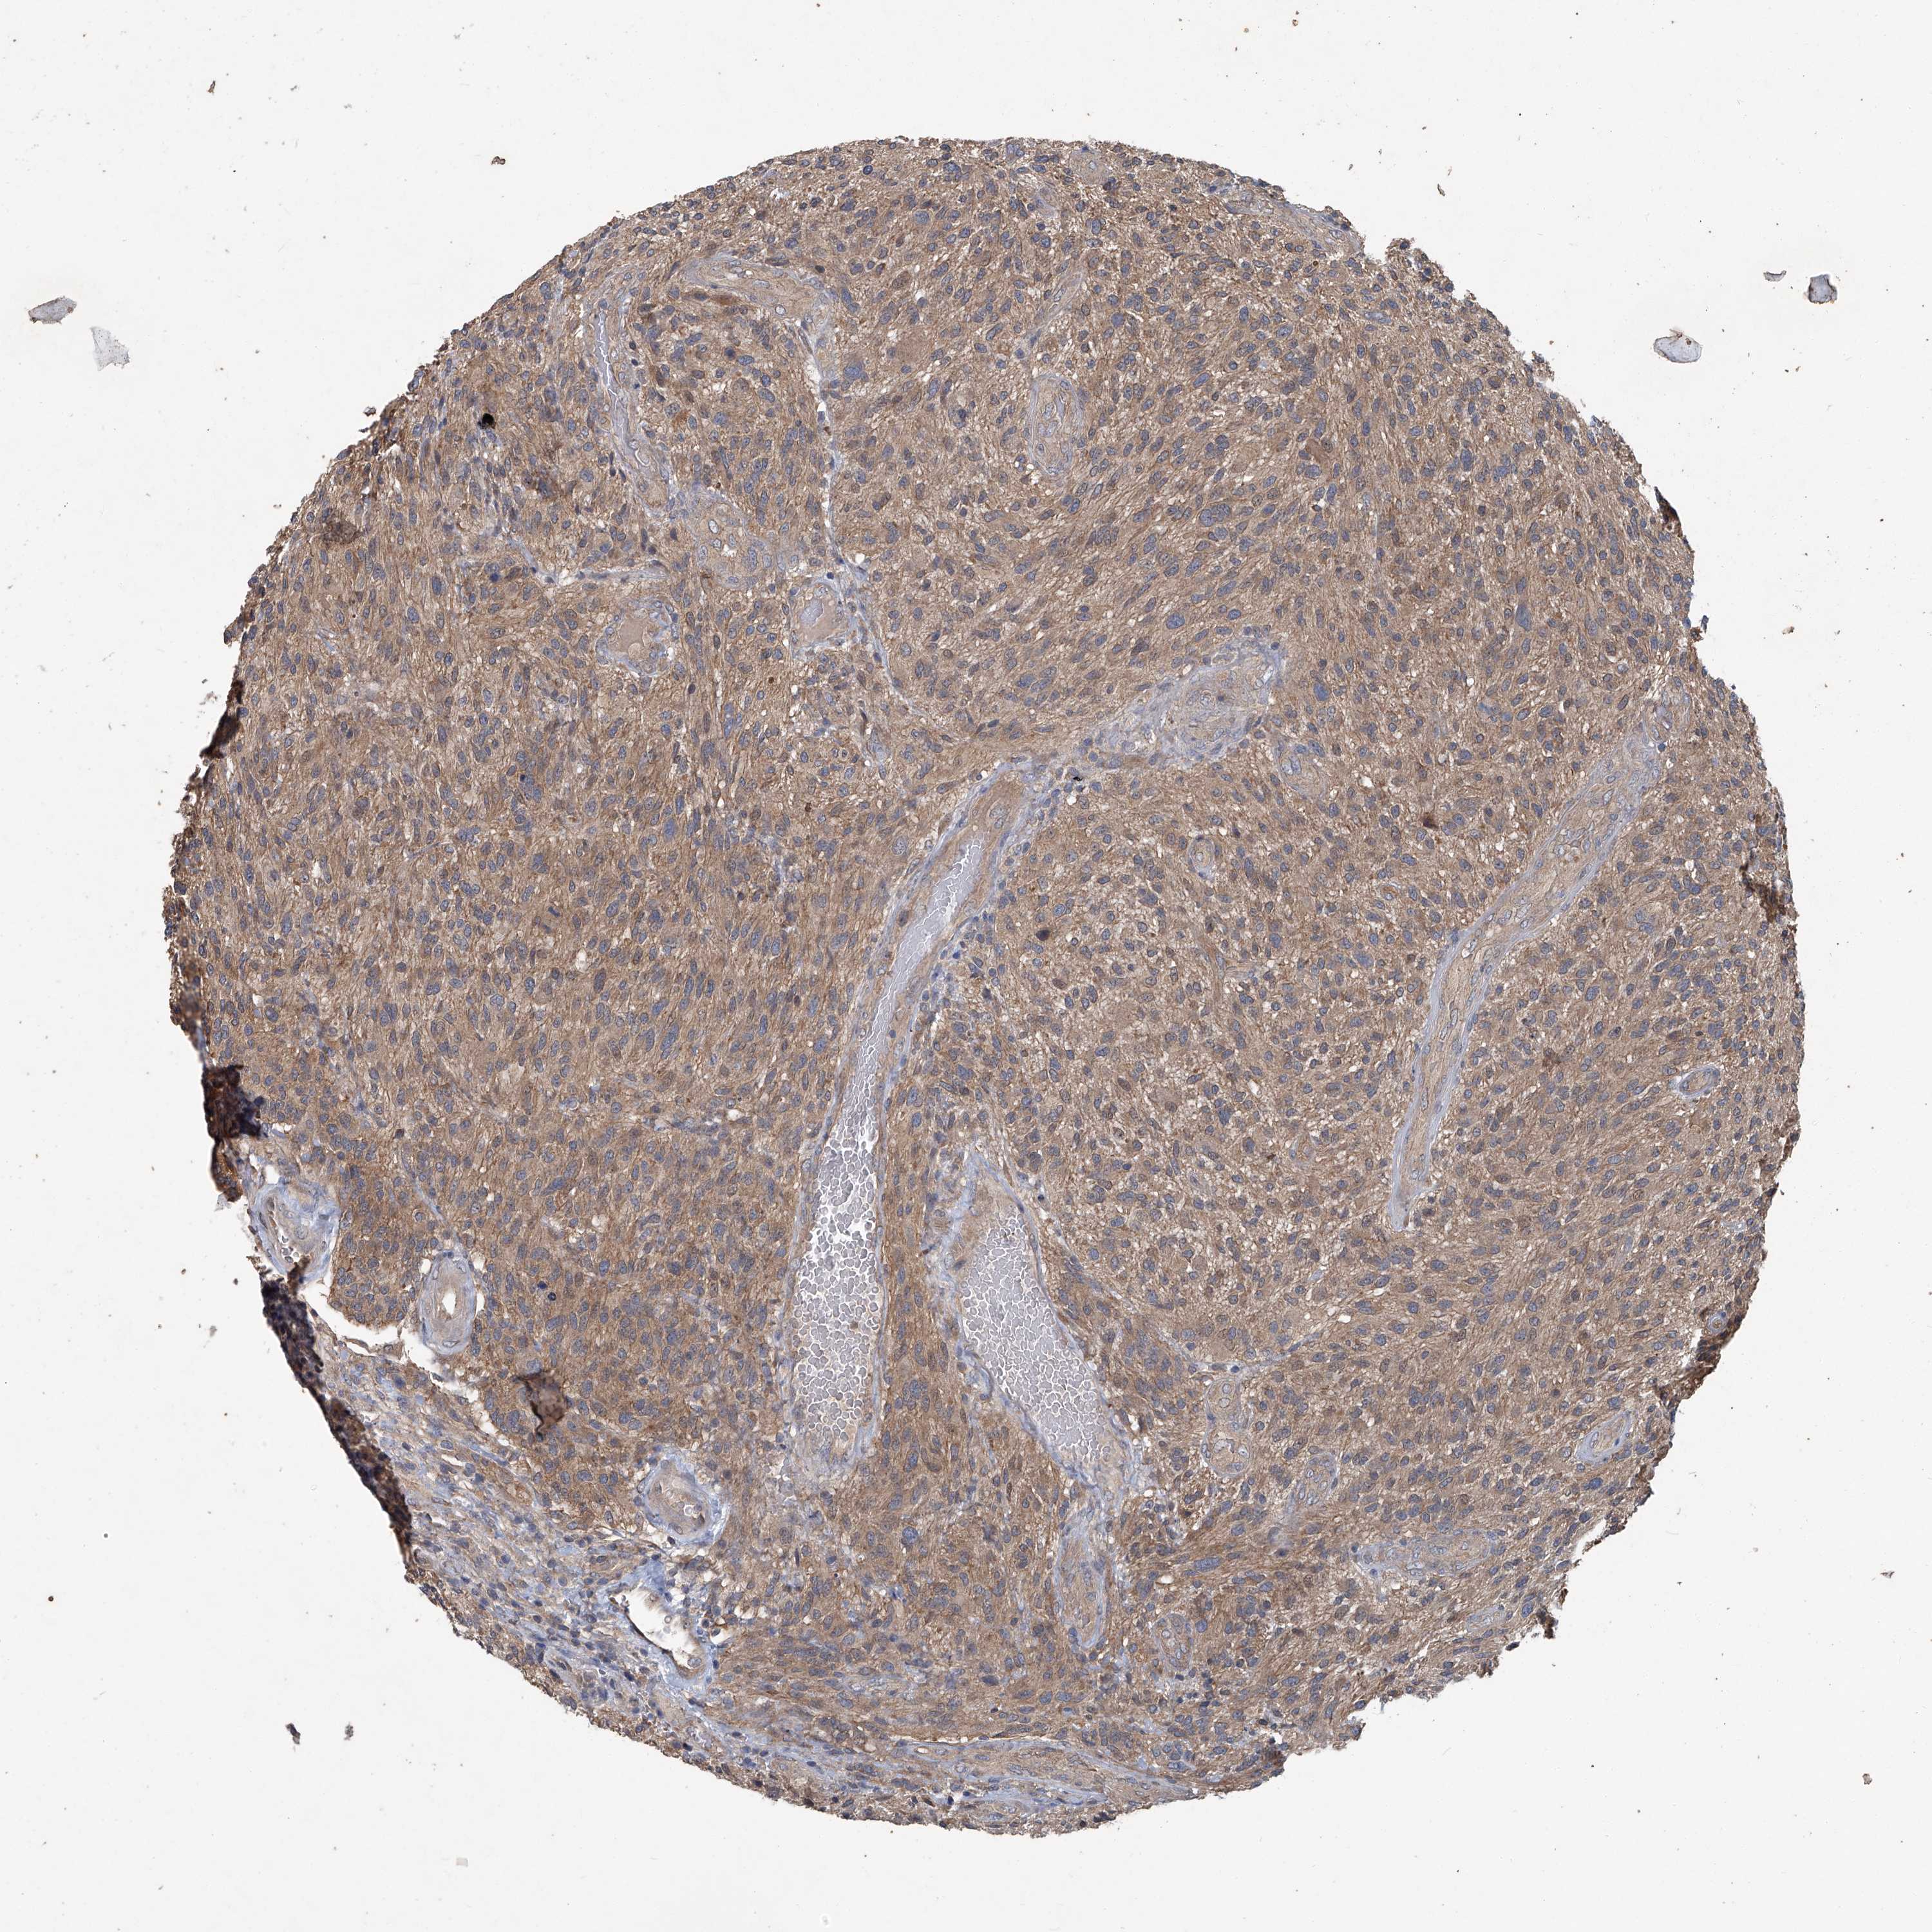

GLIOMA - Protein expressioni

A mouse-over function shows sample information and annotation data. Click on an image to view it in a full screen mode. Samples can be filtered based on level of antibody staining by selecting one or several of the following categories: high, medium, low and not detected. The assay and annotation is described here.

Note that samples used for immunohistochemistry by the Human Protein Atlas do not correspond to samples in the TCGA dataset.

Antibody stainingi

Antibody staining in the annotated cell types in the current human tissue is reported as not detected, low, medium, or high, based on conventional immunohistochemistry profiling in selected tissues. This score is based on the combination of the staining intensity and fraction of stained cells.

Each image is clickable and will lead to virtual microscopy that enables deeper exploration of all samples and also displays staining intensity scores, fraction scores and subcellular localization as well as patient and tissue information for each sample.

Antibody HPA029642

Antibody HPA029643

Glioma, malignant, High grade

Glioblastoma, NOS